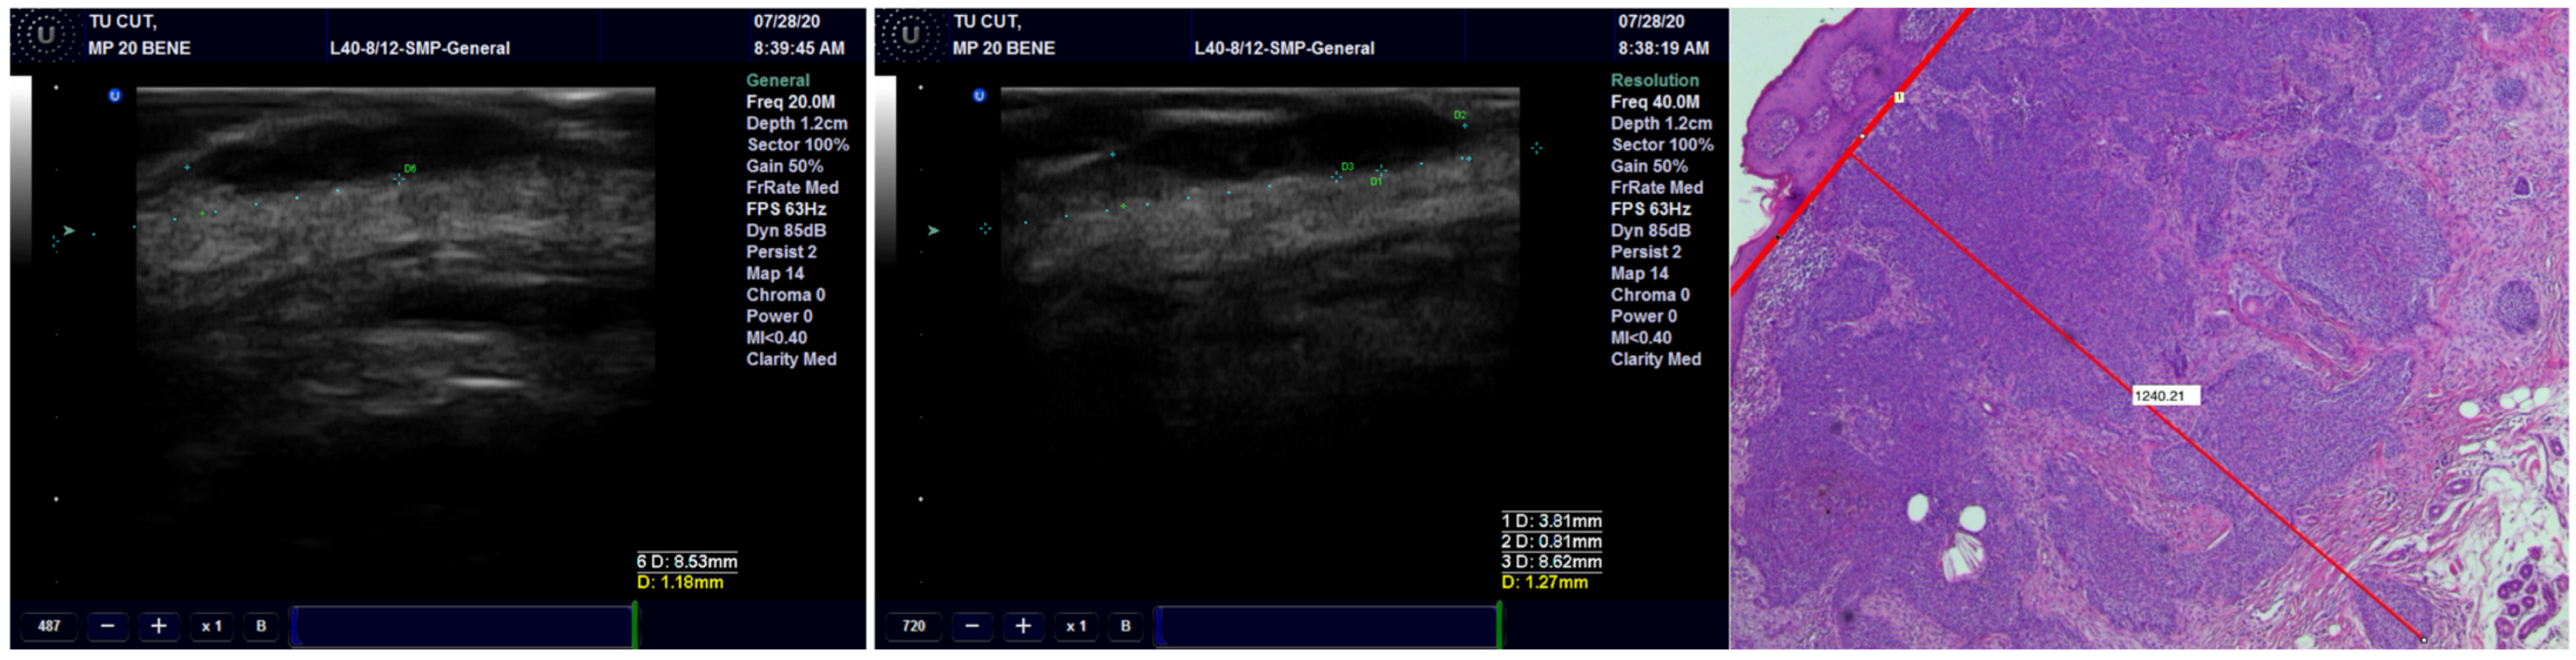

We found a very high correlation between the ultrasound measurement of the surgical margins and pathological reports, with the best result being achieved with the 13 MHz transducer, followed by the 20 MHz and 40 MHz transducers (Figure 8) (Table 5).

Figure 8.

Surgical margins measurement by US and histopathology.

Regarding the role of US in the treatment of NMSC, few studies concluded that US can easily detect malignant involvement of the margins. This may play a role in the treatment of skin cancer and prevention of local recurrence, providing improved overall survival rates. The adjacent normal tissue is measured from the limit of the tumor to the surgical resection margin. It can be easily measured on grayscale examination or elastography [44,45]. Our findings regarding the evaluation of surgical margins postoperatively illustrate the utility of this technique for immediate measurement of surgical margins directly in the operating room. All three transducers (13, 20 and 40 MHz) have shown very good results, but the most accurate was the 13 MHz transducer. This can be explained by how the lower the frequency, the deeper or greater penetrance a sound wave has. If positive or close margins are visualized, the surgery can be completed immediately. This way, the surgeon can avoid insufficient resection of the tumor or unnecessary sacrifice of healthy tissue. All these should reduce the recurrence rate and improve overall survival, but further studies are necessary to ascertain this fact.